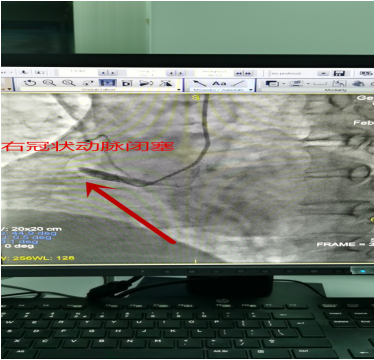

术前造影:右冠状动脉近段以远急性闭塞,如果不及时开通病变血管,患者随时可能出现死亡!